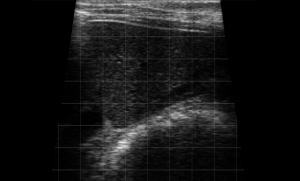

SIMON Ultrasound Database

This ultrasound database is a free resource for students and doctors!

Our collection includes videos of dogs, cats, horses, cows, humans, and many other species!